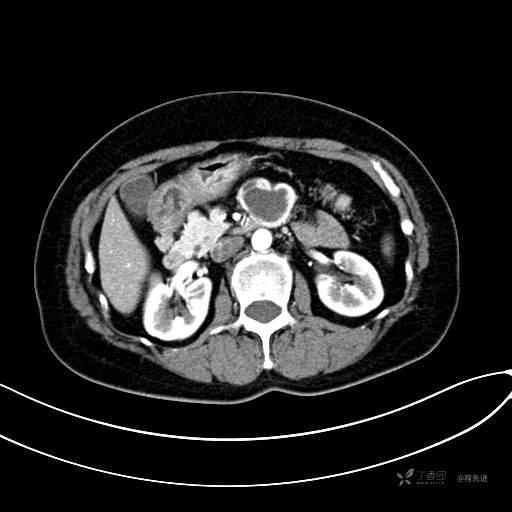

CT增强门脉期